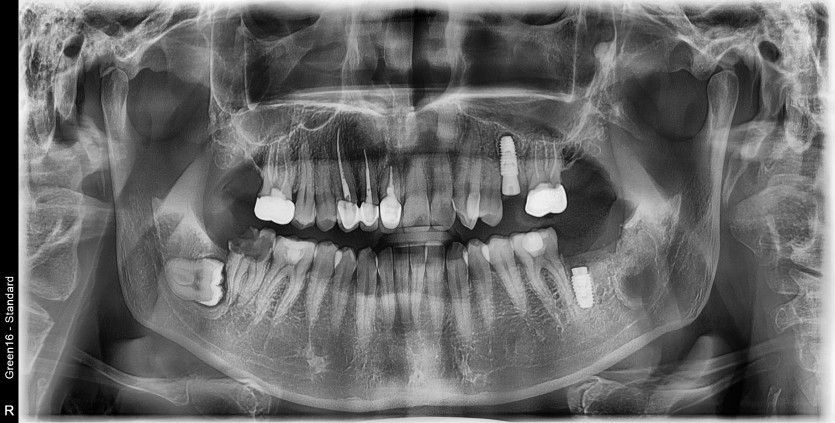

#38 사랑니 발치

구강 외과 전문의가 당일 발치했습니다.